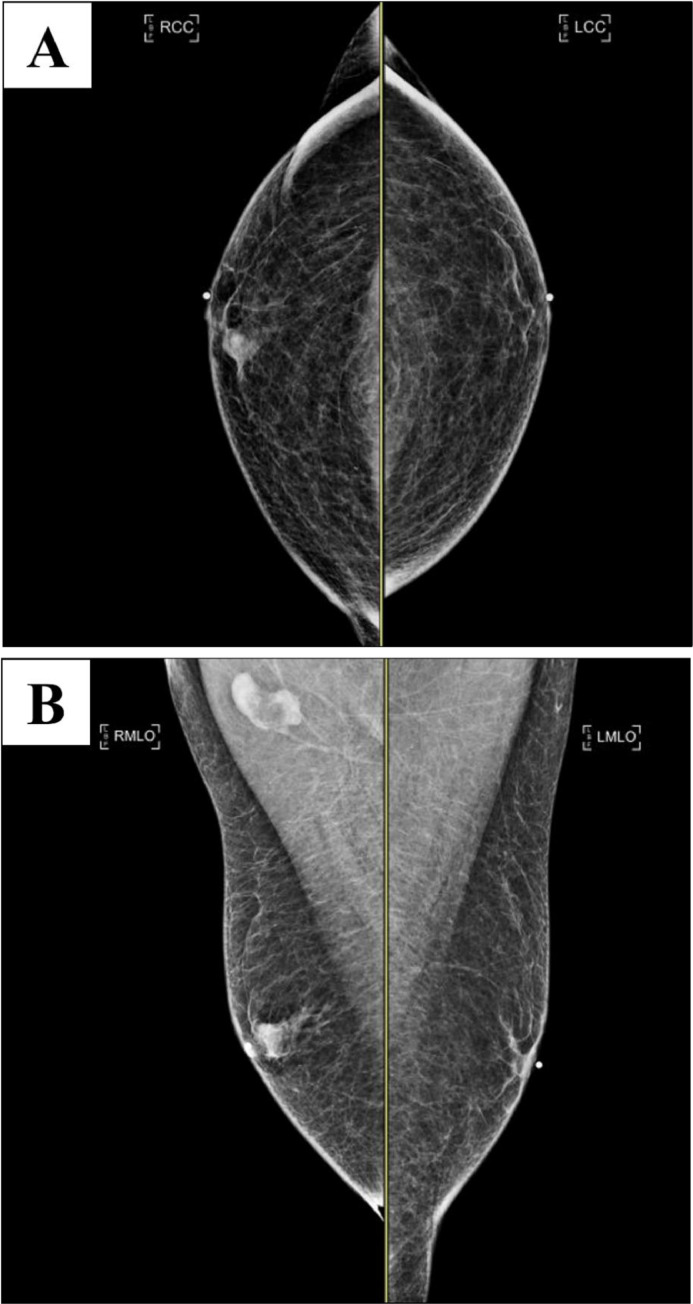

Bilateral diagnostic mammograms were obtained and showed a right breast mass at 1-o'clock located 1 cm from the nipple with indistinct margins (Fig. 6). The mass correlated to the palpable mass and bloody nipple discharge in the right breast.

Fig. 6.

Bilateral craniocaudal (A) and mediolateral oblique (B) mammograms display a right breast mass with indistinct margins at 1-o'clock located 1 cm from the nipple. BB markers are placed on the nipples and a triangular marker is placed at the area of palpable concern. There is a mild enlargement of right axillary lymph nodes.

There is a mild enlargement of the right axillary lymph nodes (Fig. 6). A focused ultrasound was obtained for further evaluation of right breast mass. A round, isoechoic, mass with indistinct margins, and internal vascularity measuring 12 mm in the right breast at 1-o'clock located 1 cm from the nipple was observed (Fig. 7). Elastography was used and showed the mass was hard (Fig. 7).